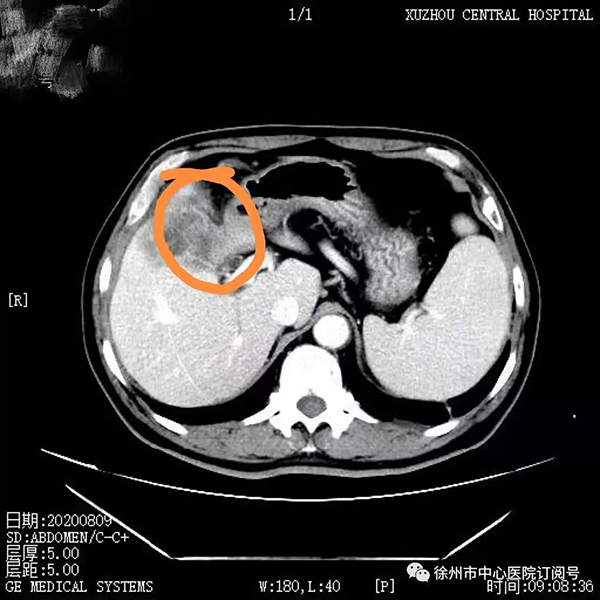

2020年8月,董先生因反復(fù)腹痛再次到徐州市中心醫(yī)院就診,結(jié)合腹部增強(qiáng)CT、MRCP、PET-CT,穿刺病理證實(shí),以及抽血化驗(yàn)指標(biāo)提示腫瘤指標(biāo)CA199升高,患者診斷膽囊癌侵犯肝臟、腹腔淋巴結(jié)轉(zhuǎn)移明確。

2020年8月腹部增強(qiáng)CT提示:膽囊壁增厚,考慮膽囊癌侵犯肝臟可能,膽囊結(jié)石合并膽囊炎癥,肝內(nèi)膽管輕度擴(kuò)張、積液。